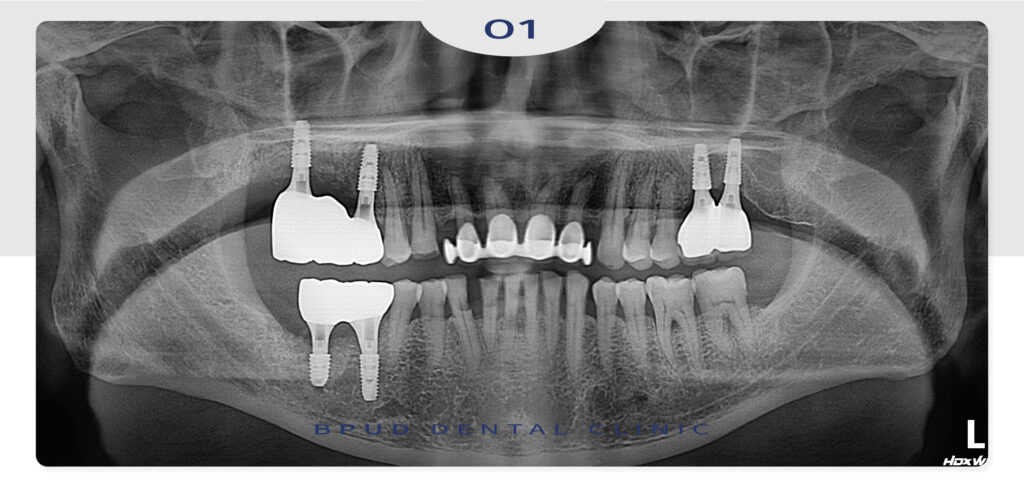

많은 양의 뼈이식을 동반한 임플란트

식립을 마친 모습입니다.

25.12.02

이어서 최종 보철물까지 문제 없이

마무리를 하였는데요.

아래쪽의 경우에도 신경관과 거리가 가까워

매우 주의하며 식립을 진행하였고

염증 조직 또한 깨끗이 제거하여

다른 곳에서 치료가 어렵다고 한 부분까지

해결이 가능하여 환자분께서도 매우 만족하셨습니다.